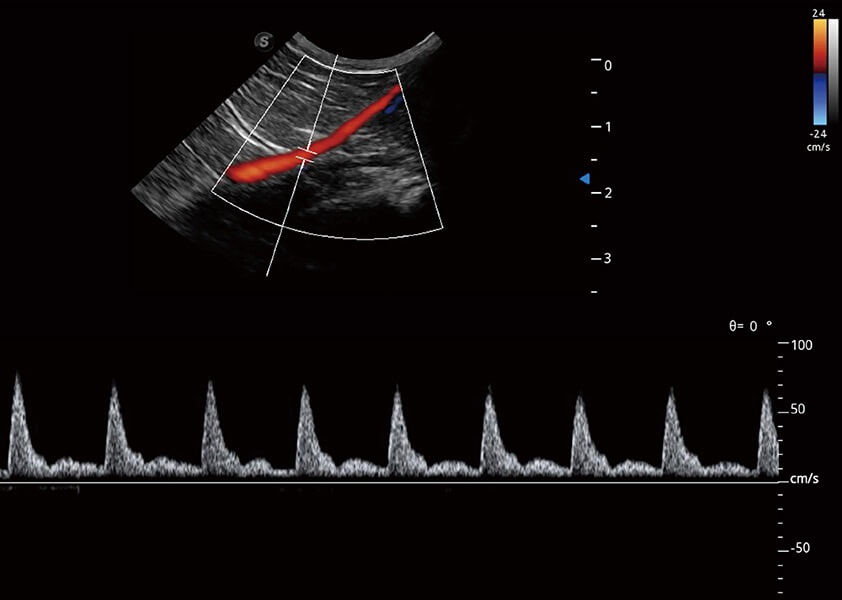

ProPet 60 作为一款高端台式动物超声设备,为动物医生的日常诊断提供了一系列贴合动物临床需求、解决临床实际问题的高级成像功能。凭借全系列高清探头,满足医生对腹部、心脏、生殖、浅表、肌骨等成像的所有需求,切实帮助您提升检查效率,提高诊断信心。